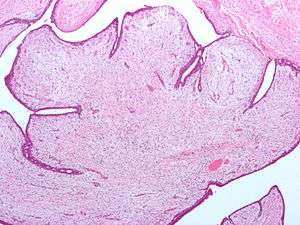

| Fibroepithelial neoplasm (Phyllodes tumor). | |

Fibroepithelial neoplasms (or tumors) are biphasic tumors. This means they consist of epithelial tissue, and stromal or mesenchymal tissue. They may be benign or malignant.[1]

- Phyllodes tumor of the Breast